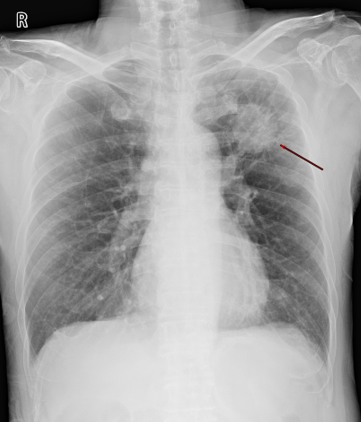

近日,梁伯(化名)来到广州医科大学附属第一医院肝胆外科复诊,一年前他曾因肺癌肝转移来到这里,汪国营教授团队给他实施了肝癌切除手术,复查发现术后恢复良好,至今没有复发。 2020年4月,梁伯因左上肺鳞癌接受了肺癌根治手术,术后坚持定期到医院复查。原本以为肿瘤切除了就“万事大吉”了,去年5月底,再次复查胸腹部CT时发现,梁伯的肝脏有一个明显的占位性病变,大小约4*2cm,考虑是肺癌肝转移。 得知“肿瘤转移”之后,梁伯及家属非常担忧,在推荐下慕名来到广州医科大学附属第一医院肝胆外科主任汪国营教授的门诊。经过详细查看和初步了解病史之后,汪国营主任对梁伯的病情已心中有数,安慰他先安心住院检查,接受进一步的治疗。

“综合各项检查评估,目前考虑为肺癌肝转移,但值得庆幸的是,暂没有发现其他器官有转移,只有肝脏上面有一个转移病灶,位于肝脏S8段,这就有了手术切除的可能。”汪国营主任提出,患者安全是首位,必须要在保证肿瘤完整切除的同时,避免大出血,将手术风险降至最低,“因为肿瘤紧贴血管,并且患者有多年抽烟史,合并慢性阻塞性肺疾病10多年,是非常明显的桶状胸。”